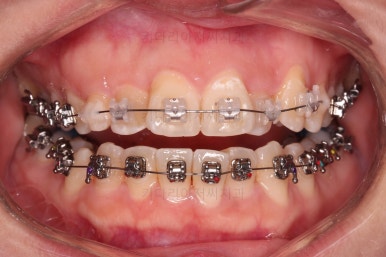

치료 종료 시 입안의 모습입니다.

윗니만 발치를 했지만 교합이 잘 맞고요.

한 쪽 송곳니가 없지만 기능적으로 전혀 문제를 못느끼실 교합을 맞춰놨고요.

위아랫니 가지런해졌고요.

대신 중앙선은 약간 틀어져 있는데요.

한 쪽은 송곳니가 없고 한 쪽은 작은 어금니를 발치했기 때문인데요.

18개월이라는 짧은 기간동안 부정교합, 덧니, 심지어 매복치아까지 개선했는데 양측 치아 사이즈 문제로 생기는 중앙선 정도는 아무 문제가 안되는거죠.